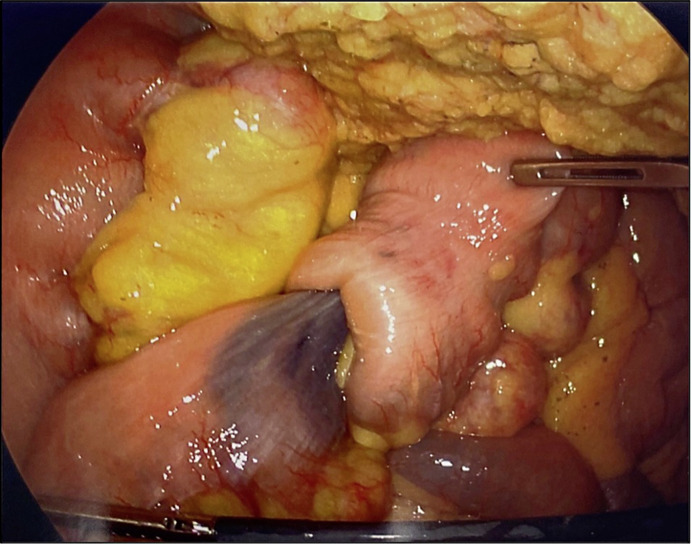

Case presentation: A 70-year-old male with Crohn's disease and chronic anemia presented with recurrent obscure gastrointestinal bleeding. Initial endoscopy was unremarkable, but capsule endoscopy identified a bleeding jejunal lesion. Double-balloon enteroscopy and imaging confirmed a jejunal lipoma causing intermittent intussusception. Due to persistent anemia, the patient underwent laparoscopic resection, with pathology confirming an ulcerated lipoma. His anemia resolved postoperatively.